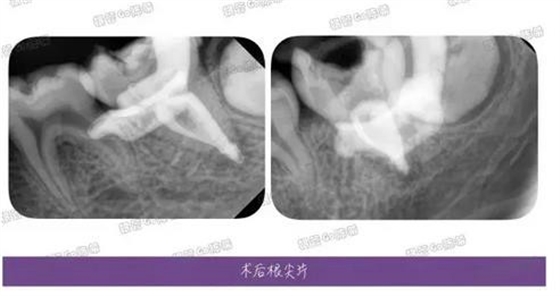

完成充填后的多角度根尖片,檢查根充效果,之前有幾個(gè)病例糊劑超填得明顯,所以做了一定的改正。

這例看來(lái)是控制得稍微好點(diǎn)了,繼續(xù)努力~